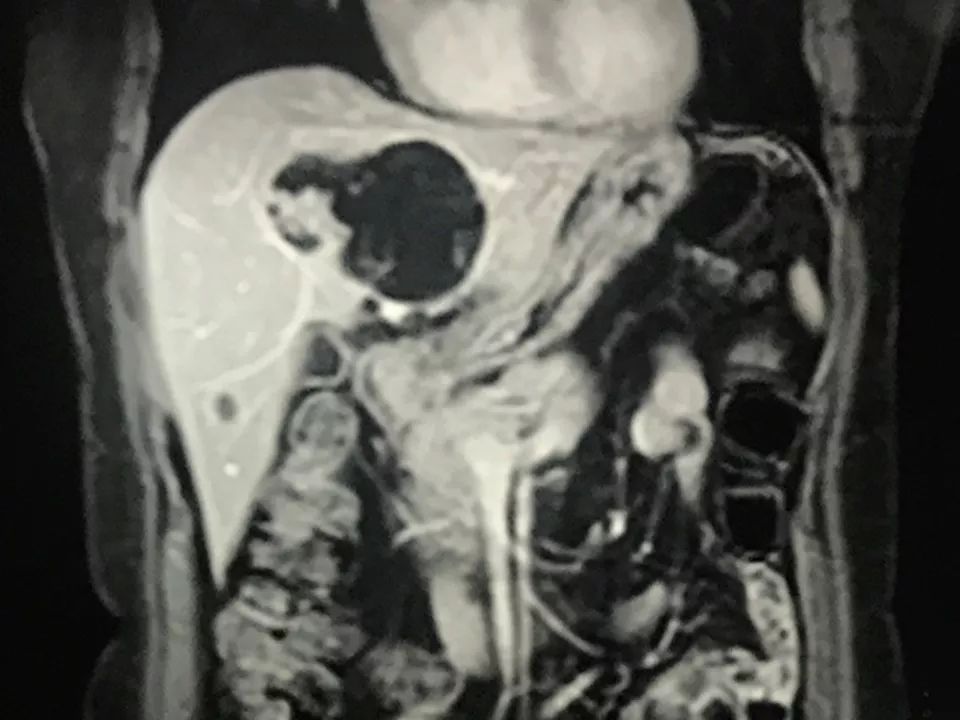

MRI表现:

肝内单发占位灶,累及肝左右叶及尾叶。T1WI示病灶以低信号为主,边缘多枚等信号结节,正反相位未见明显脂肪成份;T2WI示病灶以粘液成份为主呈高信号,边缘多枚稍高信号结节(相对肝实质),DWI呈不均匀等高信号,ADC图以高信号为主。动脉期病灶边缘均匀强化,壁结节显著强化,门脉期边缘仍持续强化,边缘光滑,壁结节呈相对等低信号。MRCP示胆管扩张,病灶与胆管相通。